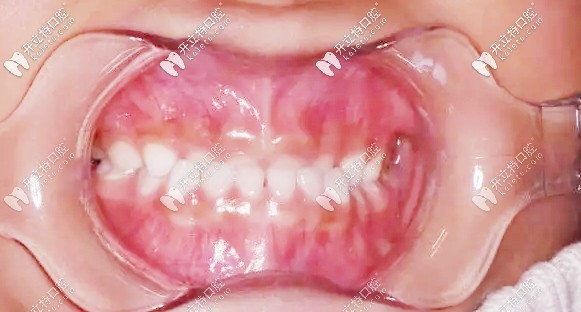

矯正前牙齒地包天

我孩子現(xiàn)在3歲零4個(gè)月,檢查結(jié)果:現(xiàn)在是乳牙期,出現(xiàn)乳牙反合,也就是地包天,醫(yī)生建議做矯正,作為新手寶媽,當(dāng)時(shí)的我是崩潰的~